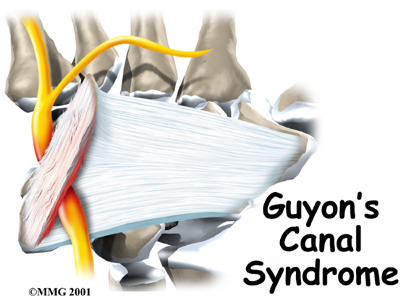

Guyon's Canal Syndrome

Guyon's canal syndrome is an entrapment of the ulnar nerve as it passes through a tunnel in the wrist called Guyon's canal. This problem is similar to carpal tunnel syndrome but involves a completely different nerve. Sometimes both conditions can cause a problem in the same hand.